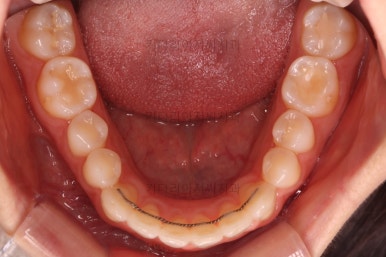

벌써 치료 종료시의 모습입니다.

치료는 총 5개월이 걸렸네요.

일반적으로 부분교정은 6개월 전후로 치료기간이 걸리긴 하고 이번 환자분의 경우는 삐뚤어진 정도가 심한 편이 아니라서 짧게 걸린 편이었어요.

치료결과는 매우 만족하셨습니다.

삐뚤었던, V자로 꺾여있던 나비앞니치아가 가지런해졌어요.

양치질도 훨씬 편해져서 장기적으로 구강건강에도 도웅미 되실 거에요.

다시 틀어지지 말라고 앞니 안쪽에 유지장치를 부착해 주고 마무리를 했습니다.